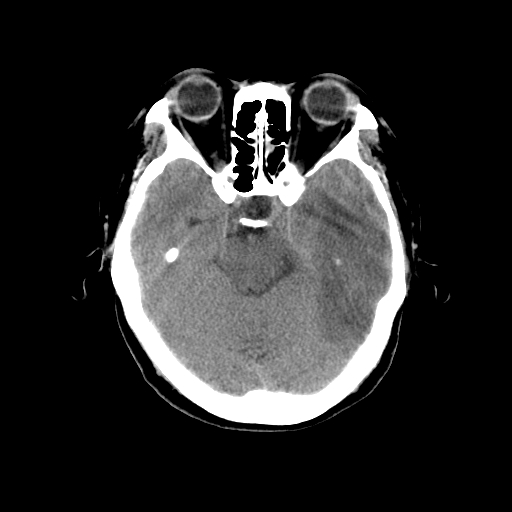

标题: CT14513:女性41岁,头部不适二月余,其它病史不详。请分析 [打印本页]

标题: CT14513:女性41岁,头部不适二月余,其它病史不详。请分析

1.考虑:左侧颞顶叶星形细胞瘤。2.大脑镰下疝。

支持!但楼主所提示处颅骨明显受压变薄,是否有合并蛛网膜囊肿或局部硬膜下水瘤的可能?脑穿通畸形暂不予以考虑:明显占位表现;病侧脑室无扩张;病灶不是较明确的脑脊液密度;边界不清晰。还是mri检查吧,提供的有价值信息更多一些,至少可以排除或肯定蛛网膜囊肿或局部硬膜下水瘤的存在。

左侧颞顶叶星形细胞瘤,建议增强

胶质瘤可能性大支持2-3级星形细胞瘤

1)考虑左侧颞顶叶胶质瘤。2)左侧颞顶部慢性硬膜下血肿?3)大脑镰下疝。